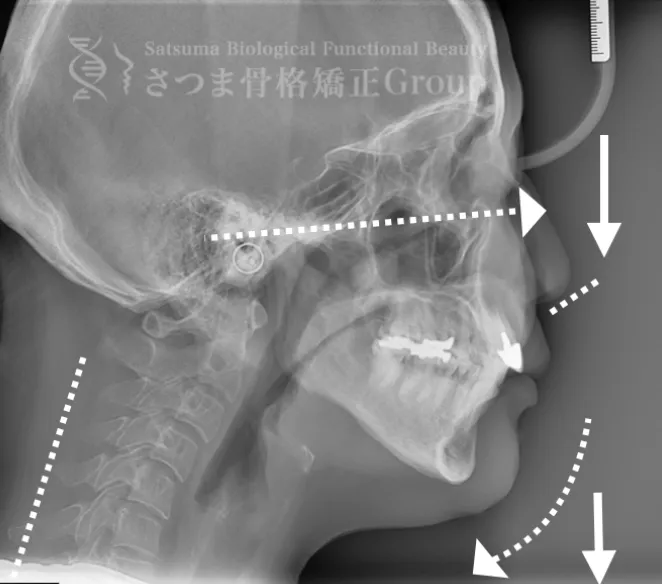

これらの問題を正確に評価するため、当院では セファロシステムによるレントゲン撮影(X-ray images) を行っています。

セファロ撮影によって 顎関節・頭蓋骨・頸椎の位置関係を客観的に可視化でき、施術前の状態を科学的に把握することが可能となります。

• 顎位のズレ

• 咬合の乱れ

• 頭位・頸椎姿勢のバランス

• 筋肉・関節の負担部位

施術の前後で撮影したレントゲン写真を比較することで、改善の度合いや変化を一目で確認できます。